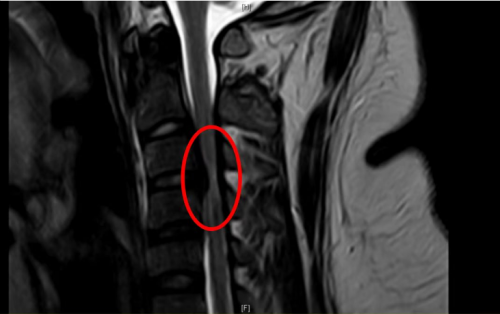

标红部位提示颈椎椎管狭窄、脊髓受压变性

“患者体重高达320斤,属于重度肥胖,且合并高血压,经过完善核磁检查,诊断为脊髓型颈椎病、颈椎椎管狭窄、颈椎后纵韧带骨化,由于病情严重,已经造成颈椎椎管狭窄、脊髓受压变性。”91短视频